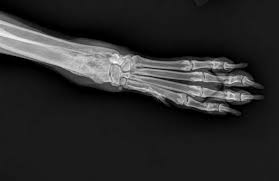

Signs Of Bone Cancer In Dogs Leg - Dr Wiltzius Shares Canine Bone Cancer Diagnosis Staging And What To Expect - Osteosarcoma is a word derived from osteo, meaning bone, and sarcoma, meaning cancer.. They can include swelling, lameness, and joint or bone pain. Veterinarians often use the phrase away from the elbows & toward the knees to remember the anatomically predisposed sites, including: Dog bone cancer warning signs sometimes bone cancer makes a sudden appearance as a lump in the leg, or in worst case scenario, as a pathologic fracture. When the tumor first appears, the site usually looks slightly swollen. Or a dramatic, sudden fracture.

Other types of bone cancer include chondrosarcoma, fibrosarcoma, and hemangiosarcoma. Osteosarcoma is a common dog cancer in large breeds, and it most often affects the long bones of the legs. Most dogs will show signs of swelling and soreness in limbs close to joints. Usually, osteosarcoma develops in the long bones of the front legs, though the rear legs, jaw, face. Symptoms of bone cancer in dogs: If you decide to proceed with amputation, you will admit your pet into the hospital either the day before or the morning of surgery. Canine bone cancer may be part of the diagnosis. Sometimes a biopsy is performed by taking a small piece of bone and testing it. They can include swelling, lameness, and joint or bone pain. The early signs of bone cancer in dogs can difficult for pet parents to recognize since symptoms tend to be subtle. Symptoms and types many signs of bone cancer are subtle. (most dogs with this kind of cancer do not survive beyond a year with amputation alone. Canine bone cancer symptoms osteosarcoma tumors typically form in a dog's long bones, or growth bones, and are found frequently below the elbow or near the knee or shoulder.

Dog bone cancer warning signs sometimes bone cancer makes a sudden appearance as a lump in the leg, or in worst case scenario, as a pathologic fracture. As the tumor continues to grow, the bone containing the tumor will expand. Washington ( circa) — osteosarcoma (osa) is one of the most common forms of bone cancer seen in veterinary patients. Osteosarcoma is a type of bone cancer. Other types of bone cancer include chondrosarcoma, fibrosarcoma, and hemangiosarcoma. Since we can't ask our dogs how they are feeling each day, it's important to understand the signs of a sick dog. How to help our mastiff with bone cancer. While tumors usually occur in the long bones of the limbs, osteosarcoma can affect any bone. It's the cancer of the bones. Osteosarcoma is the most common bone cancer in dogs. Symptoms of bone cancer in dogs: Osteosarcoma (osa) at the top of the list, osteosarcoma is the most prevalent type of bone cancer in dogs. Sometimes a biopsy is performed by taking a small piece of bone and testing it.

Osteosarcoma Bone Cancer In Dogs from www.aspcapetinsurance.com Sadly, the outlook for a dog with an osteosarcoma. While tumors usually occur in the long bones of the limbs, osteosarcoma can affect any bone. This bone cancer grows very quickly and frequently spreads to other areas of the body, especially lymph nodes, lungs and other bones. The total length of anesthesia time is usually three to four hours. Lameness caused by osteosarcoma is typically mild at the onset, but then progresses over time. Osteosarcomas are painful tumours that often first appear as hot, solid, tender swellings. Osteosarcoma is a type of bone cancer. Sometimes a biopsy is performed by taking a small piece of bone and testing it.